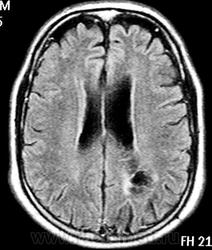

ГМ. Субэпендимома 2. +

Субэпендимома